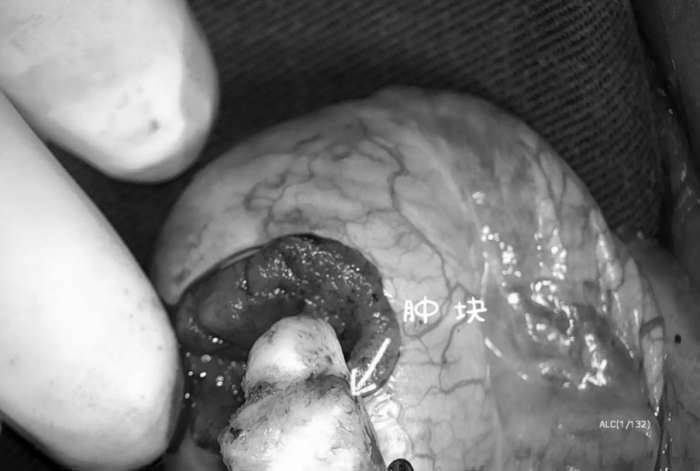

經(jīng)泌尿外科團(tuán)隊(duì)討論后完善手術(shù)方案,決定為小張行“顯微鏡下睪丸腫瘤剜除術(shù)”。手術(shù)中沿著腫塊的邊緣切開,在顯微鏡的放大作用下,腫塊周圍的血管和曲細(xì)精管清晰可辨,曲細(xì)精管用顯微鑷小心剝離,血管通過電凝進(jìn)行止血處理,術(shù)中出血很少,腫塊也完整剝出。

術(shù)后第二天小張便順利出院,術(shù)后病理也證實(shí)術(shù)前的判斷,是睪丸錯(cuò)構(gòu)瘤。